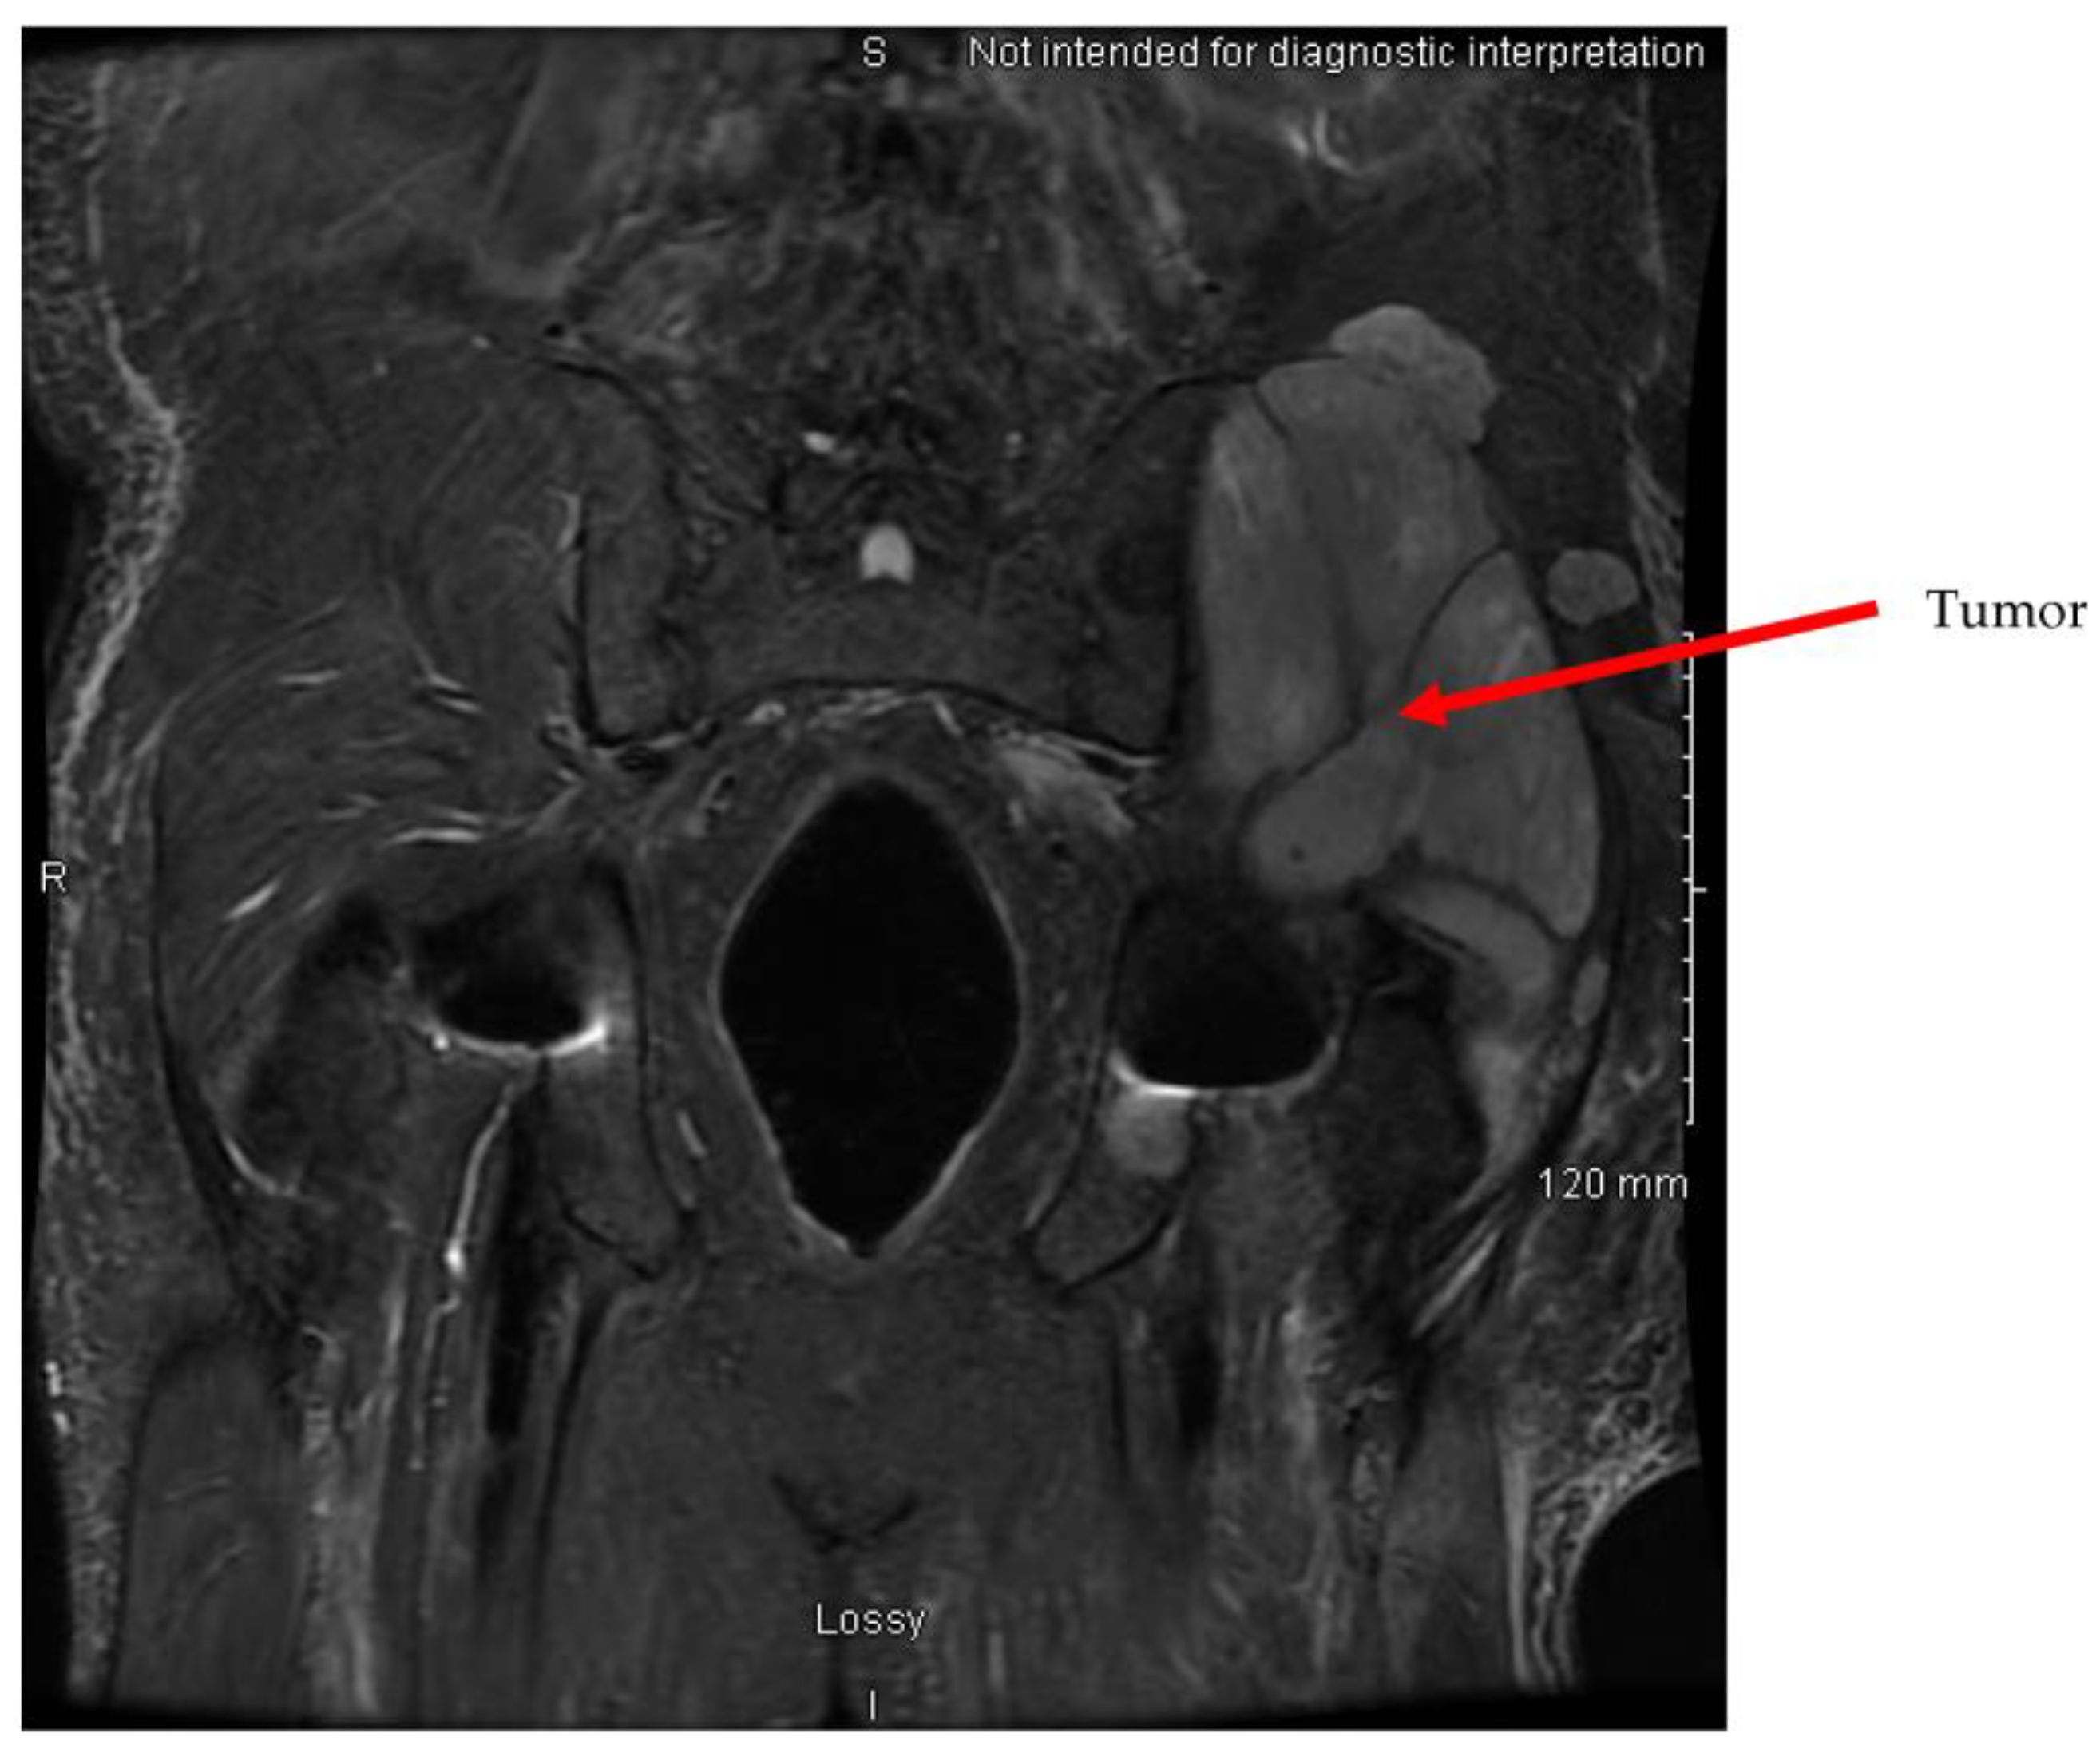

2. Case